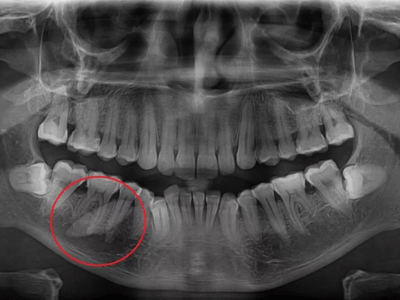

Não necessariamente. Pedras pequenas podem ser tratadas com hidratação, massagem e estimulação da salivação. Pedras maiores ou que causam obstrução significativa podem ser removidas por técnicas minimamente invasivas (sialendoscopia) ou cirurgia convencional, dependendo das características do caso.

Intervenções para remoção de obstruções ou tumores nas glândulas salivares, com planejamento individualizado para cada caso.